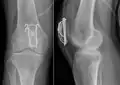

Seitliche Röntgenaufnahme einer typischen Patellaquerfraktur im unteren Teil, die Patellarsehne setzt als weicher Schatten dargestellt am unteren Patellapol an, die Quadriceps-Sehne am oberen Fragment

Röntgen

Mit einfachen Röntgenbildern des Kniegelenks in zwei Ebenen (von vorne und von seitlich) kann zuverlässig jeder Kniescheibenbruch diagnostiziert werden. Es zeigen sich die Bruchstücke auseinandergezogen und meist mit einem einfachen Quer- oder Schrägbruch, der der typischen Krafteinwirkung von vorne und dem einwirkenden Muskelzug entspricht. Damit liegt auch die Zerreißung der knorpeligen Gelenkfläche der Kniescheibe zur Oberschenkelrolle („patellares Gleitlager“) vor.